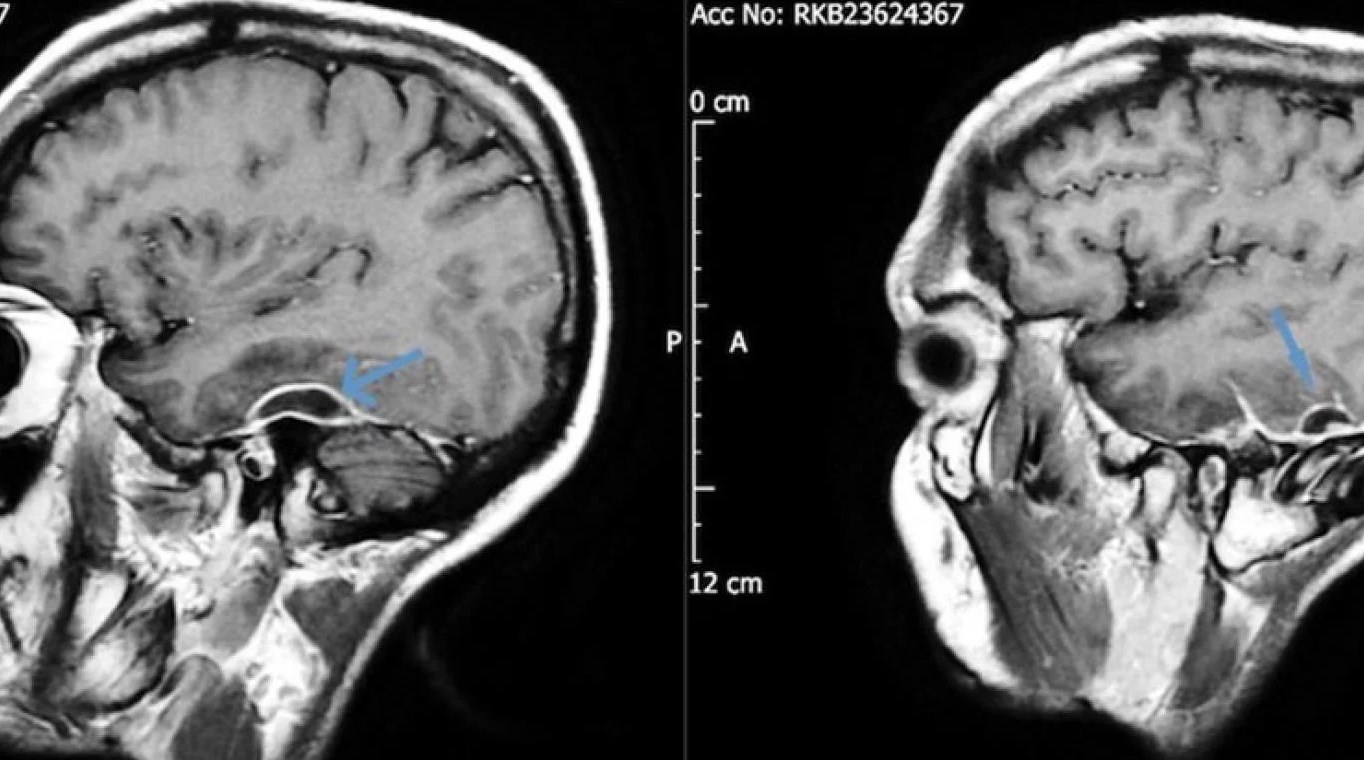

Desde el servicio de emergencias pidieron una tomografía de cabeza y encontraron en el paciente acumulaciones de pus en el tejido que rodeaba su cerebro. Los análisis de sangre revelaron que la bacteria que causó la grave infección fue la Pseudomonas aeruginosa, y se trasladó a través de un pedazo de algodón que formaba parte de un hisopo que se había desprendido dentro de la cabeza del paciente hacía años. La infección, también conocida como otitis externa necrosante, podría afectar los nervios faciales, causando secuelas similares a las de un accidente cerebrovascular. Sin embargo, en este caso y a partir del descubrimiento, se procedió a retirar el algodón con anestesia y después de ocho semanas de antibióticos intravenosos, el hombre se recuperó por completo.